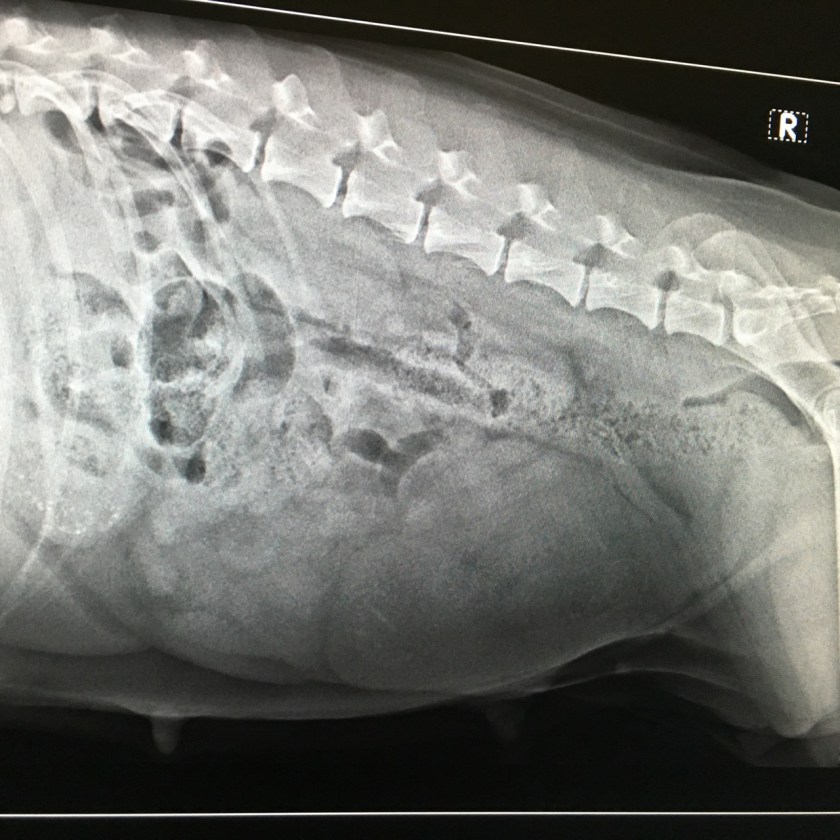

Torsdag morgen var vi hos veterinæren for å ta en røntgenundersøkelse av Bitten. Jeg ønsket å finne ut hvor mange valper hun bærer på. Ved ultralydundersøkelsen så vi bare to fosterblærer. Som nevnt i et tidligere innlegg kan det være noen utfordringer med et lite kull, blant annet sen fødselsstart og store valper. På røntgenundersøkelsen så vi 4-6 valper! Det var noe vanskelig å si antallet eksakt, og årsaken til dette kan være at skjelettet ikke er helt ferdig dannet enda. Torsdag var dag 47 regnet fra 2. parring, men det kan se ut til at befruktningen skjedde noen dager etter parringen. Hundens sædceller kan vare i flere dager etter parring. Skjelettet er ikke ferdig dannet før dag 45, så det kan bety at vi ikke er kommet helt dit enda.

Vi tok noen bilder av skjermbildet med mobilen. Vanligvis fungerer dette bra, men uheldigvis ble bildene veldig dårlige denne gangen. Bildet viser ikke valpene særlig tydelig, men hos veterinæren kunne vi telle mellom fire og seks valper. De ligger tett i tett i livmoren, omtrent som perler på en snor. Det er derfor fort gjort at de skjuler hverandre. På bildet er det mulig å se flere ryggrader og to hodeskaller.